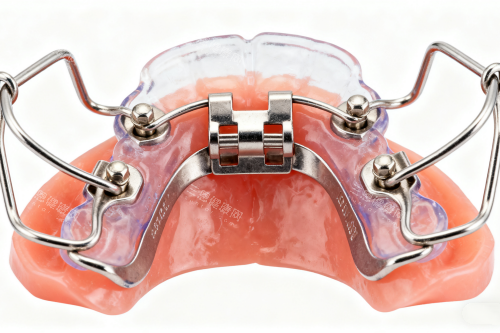

牙齿不齐不仅影响美观,还可能导致口腔健康问题。致美口腔提供的牙齿矫正服务起价6000元,这个价格通常对应的是传统的金属托槽矫正。金属托槽矫正技术成熟,结果可靠,虽然美观性稍差,但性价比很高。

对于重视外观的患者,可以选择陶瓷托槽矫正,价格约8000-15000元。陶瓷托槽颜色接近牙齿本色,远看不太明显,满足了患者对美观的需求。而隐形矫正则是目前更受欢迎的选择,通过一系列透明的可摘戴矫治器逐步移动牙齿,价格在15000-35000元之间,取决于矫正难度和治疗周期。

儿童早期干预性矫正也是致美口腔的特色服务之一。针对7-12岁儿童的肌功能矫正器价格约5000-8000元,能够利用儿童生长发育的潜力,引导牙齿和颌骨向正确方向生长,避免或减轻将来可能需要进行的复杂正畸治疗。